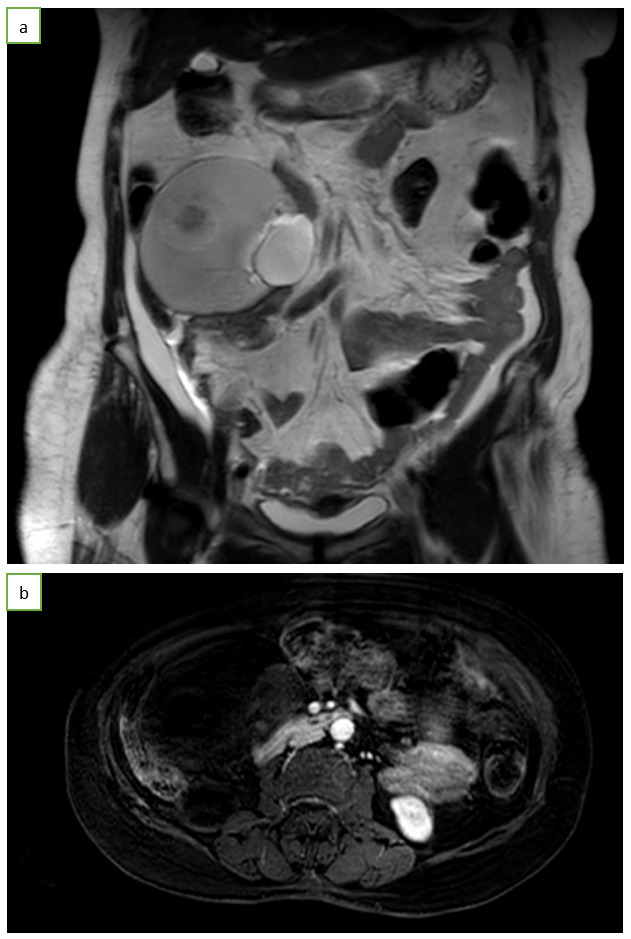

CT abdomen scan (64-slice CT scanner) with intravenous contrast showed a heterogeneous mesenteric lesion of size 10 cm × 8 cm × 10 cm with fatty, ossified, calcified, and cystic components within—findings compatible with mesenteric teratoma (Figure 1). MRI: Distinct tissue characterization, with fat appearing hyperintense on T1, fluid on T2, and occasional wall enhancement (Figure 2).

Figure 2: MR abdomen in coronal T1 (a); with intravenous contrast in axial section (b).

- MRI: Distinct tissue characterization, with fat appearing hyperintense on T1, fluid on T2, and occasional wall enhancement.